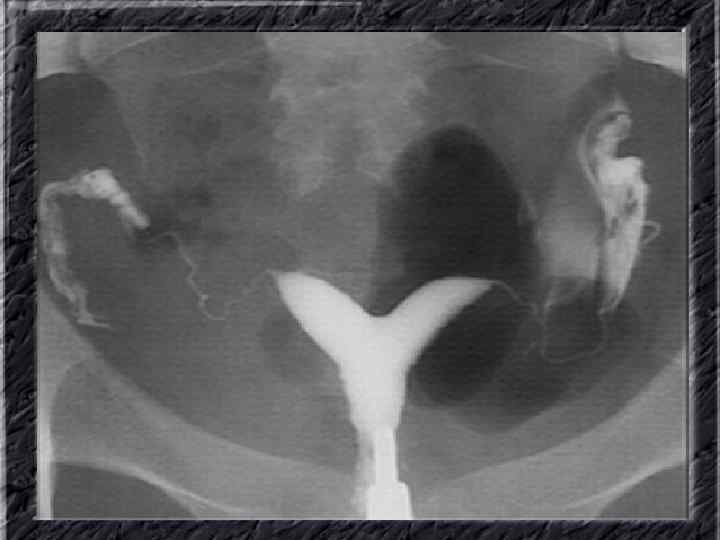

Названия слайдов: • • • Слайд 41. Лапароскопия: эндометриоидная киста яичника. Слайд 42. Лапароскопия: эндометриоидные гетеротопии на поверхности эндометриоидной кисты яичника. Слайд 43. Ультрасонография: поликистозное изменение яичника. Слайд 44. Серозная цистаденома яичника: внешний вид; макропрепарат. Слайд 45. Лапароскопия: цистаденома яичника. Слайд 46. Ультрасонография: папиллярная цистоаденома яичника, содержащая внутри папиллярные разрастания. Слайд 47. Ультраснография: многокамерная киста яичника (муцинозная цистаденома). Слайд 48. Лапароскопия: папиллярная цистаденома. Слайд 49. Ультрасонография: многокамерное жидкостное образование яичника, содержащее полиморфный солидный конгломерат — рак из муцинозной цистаденомы. Слайд 50. Рентгеноконтрастная сальпингография: нормальное наполнение и проходимость обеих маточных труб.